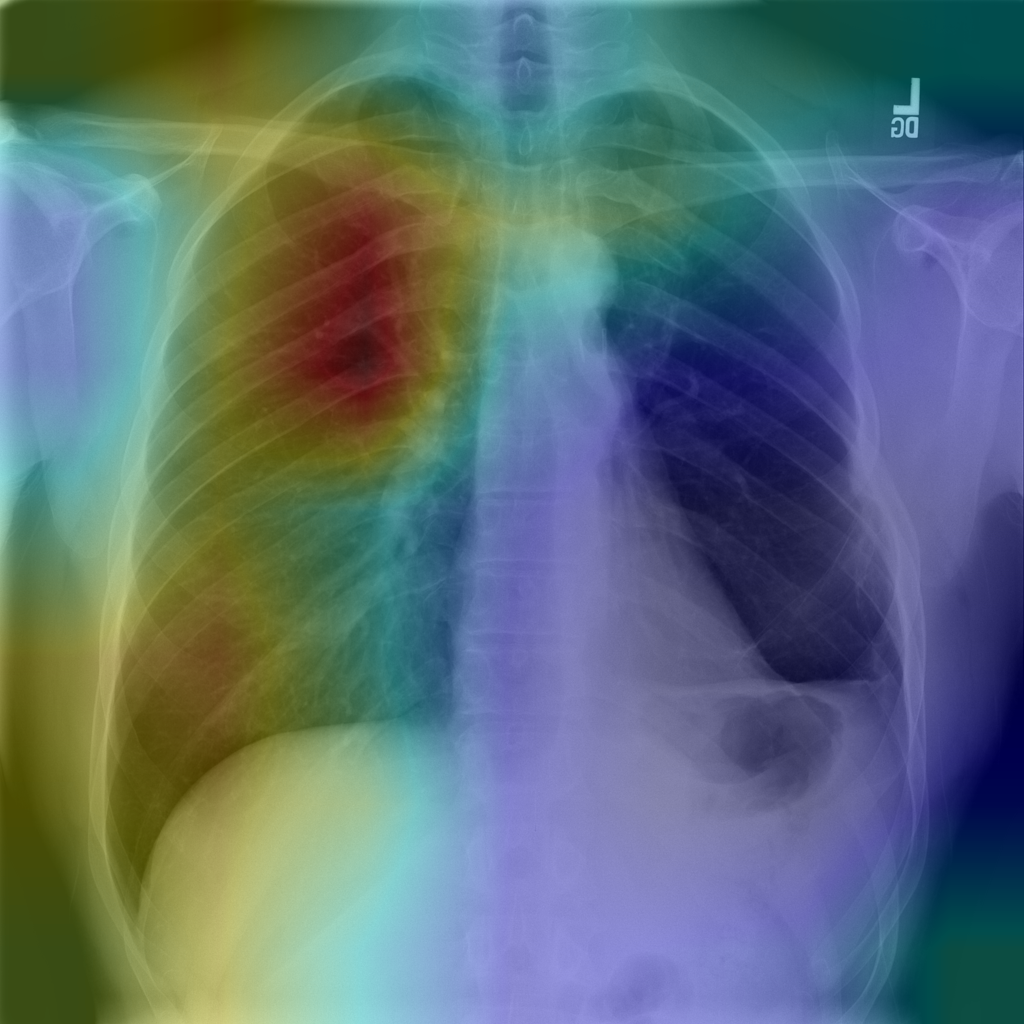

This is a Python3 (Pytorch) reimplementation of CheXNet. The model takes a chest X-ray image as input and outputs the probability of each thoracic disease along with a likelihood map of pathologies.

We followed the training strategy described in the official paper, and a ten crop method is adopted both in validation and test. Compared with the original CheXNet, the per-class AUROC of our reproduced model is almost the same. We have also proposed a slightly-improved model which achieves a mean AUROC of 0.847 (v.s. 0.841 of the original CheXNet).